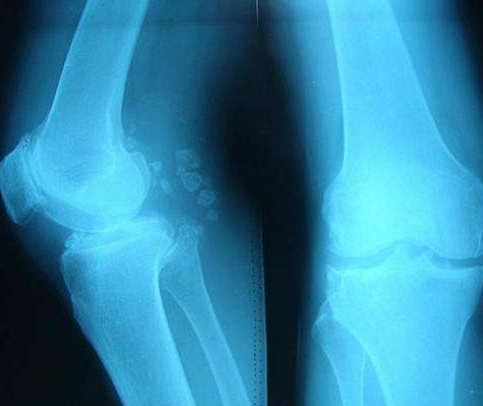

骨質(zhì)增生是生活中常見的骨科疾病,給患者帶來很大的行動(dòng)不便和影響?;忌瞎琴|(zhì)增生的原因很多是由于骨質(zhì)鈣化的情況比較的嚴(yán)重??梢苑譃檠倒琴|(zhì)增生,頸椎骨質(zhì)增生,和膝關(guān)節(jié)骨質(zhì)增生,改善骨質(zhì)增生應(yīng)該要根據(jù)發(fā)生的部位和特殊生理結(jié)構(gòu)才能實(shí)現(xiàn)徹底改善。

骨質(zhì)增生病發(fā)的原因在于外界的環(huán)境對骨骼的誘發(fā)而形成的,骨骼自身存在生理性的退變?yōu)榛A(chǔ),只有在外力不當(dāng)?shù)那闆r下從而患上腰椎骨質(zhì)增生的現(xiàn)象。這也是骨質(zhì)增生改善第一遵循原則

骨質(zhì)增生改善的第二原則為:不同部位受力情況和損耗的針對性改善。腰椎頸椎以及膝關(guān)節(jié)等身體受力不同,從而改善的力度,強(qiáng)度以及改善的角度上提出了更高的改善要求。改善骨質(zhì)增生的方法有哪些呢?